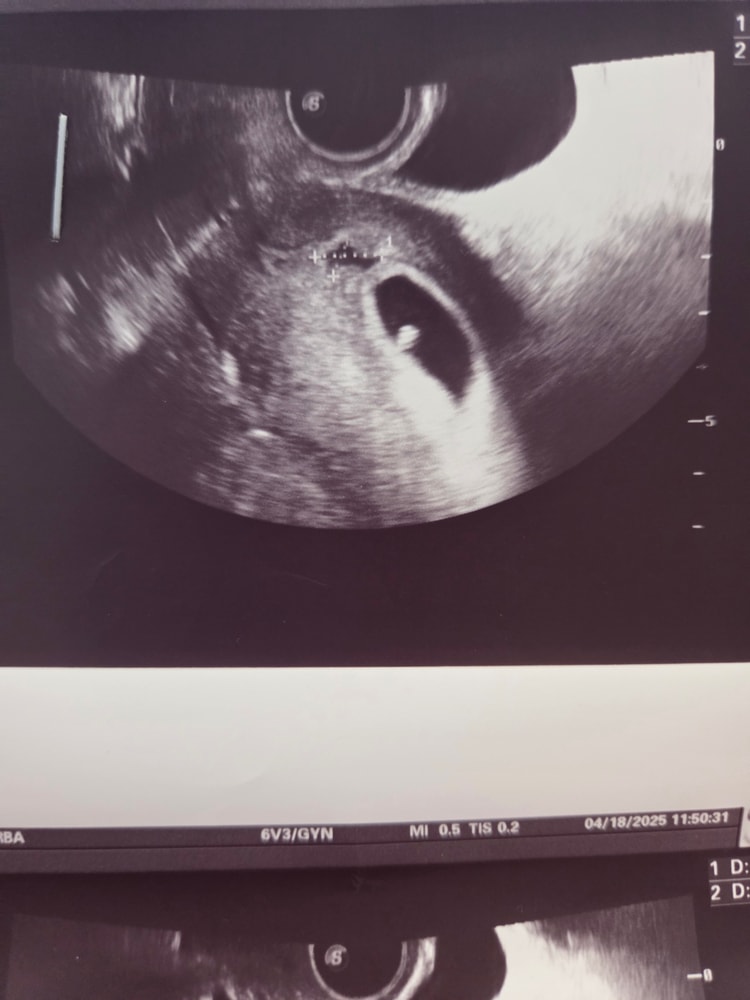

На предыдыдущем узи 18.04 в 6+6 нашли гематому 12,3 мм×7 мм,на фото видно. Сразу же сходила к гинекологу, назначили дюфастон самую маленькую дозу 2т в день, потому что не было никаких болей и выделений,все отлично по самочувствию. Этамзилат 5 дней пропить и параверин 5 дней. Ну и лежать дома нигде не шататься,мне в принципе с начавшимся токсом только этого и хотелось))